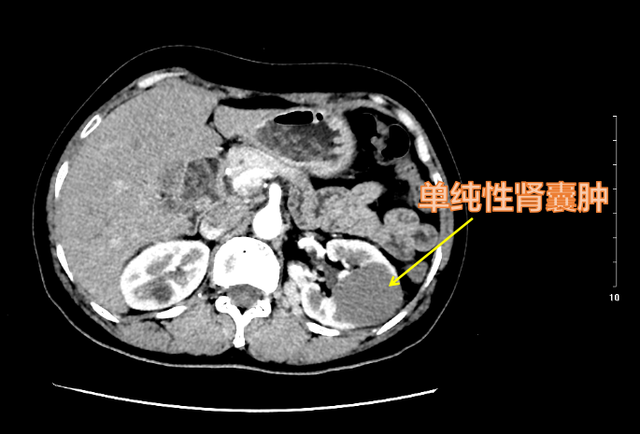

肾脏的囊性病变(也可称为囊性占位)是一种比较常见的疾病。随着老百姓健康意识的不断增强和体检中超声检查的广泛使用,全中国每年超过6000万人次进行体检,越来越多的人都发现存在肾脏囊性占位。据流行病学调查显示:肾脏囊性占位中,单纯性肾囊肿占绝大多数(>90%),总的发病率约7.7%,且年龄越大,发病率越高,≤40岁的人群发病率约为3.0%,而≥60岁则为23.0%,男性多于女性。

肾囊肿是指肾组织内出现单个或多个囊性包块,内含液体或半固体碎片。

单纯性肾囊肿边界清晰,预后良好!